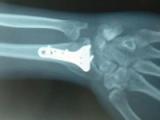

Швейцарские ученые разработали и успешно испытали на животных новый материал, который может существенно облегчить лечение сложных переломов. Исследователи предлагают использовать для изготовления спиц, шурупов и других видов креплений для костей прозрачный сплав магния, цинка и кальция.

Новый материал достаточно прочен и гибок для того, чтобы выдержать нагрузку на кость. При этом он способен медленно растворяться в организме пациента без каких-либо токсических эффектов.

В настоящее время при лечении переломов используются импланты из нержавеющей стали и титана. Такие крепления со временем изнашиваются и деформируются, в результате чего достаточно часто возникает необходимость в повторных хирургических вмешательствах. Перспективной альтернативой стальным и титановым креплениям являются крепления из биорастворимых материалов, в частности – из сплавов магния.

Незначительные количества магния, цинка и других металлов, поступающие в организм при медленном растворении такого материала, не представляют опасности для организма и быстро выводятся из него. Однако обычно этот процесс сопровождается химической реакцией с выделением свободного водорода, который может повредить живые ткани.

Группе ученых из швейцарского Государственного технологического института Цюриха под руководством Йорга Лоффлера (Jörg Löffler) удалось преодолеть это препятствие с помощью особой техники быстрого охлаждения сплава, включающего 60 процентов магния, 35 процентов цинка и 5 процентов кальция. В результате структура кристаллической решетки сплава менялась, и выделения свободного водорода при его растворении жидких средах организма не происходило.

Исследователям также удалось показать, что скорость растворения полученного ими материала можно регулировать, меняя содержание в нем цинка. Это дает дополнительную возможность для регулирования продолжительности срока, в течении которого крепления разного назначения будут выполнять свою функцию. Биосовместимость и безопасность нового материала подтверждена опытами на животных. Однако, по признанию ученых, для того чтобы обосновать целесообразность его использования в медицине, потребуются дополнительные лабораторные эксперименты.

Работа исследователей опубликована в Nature Materials.